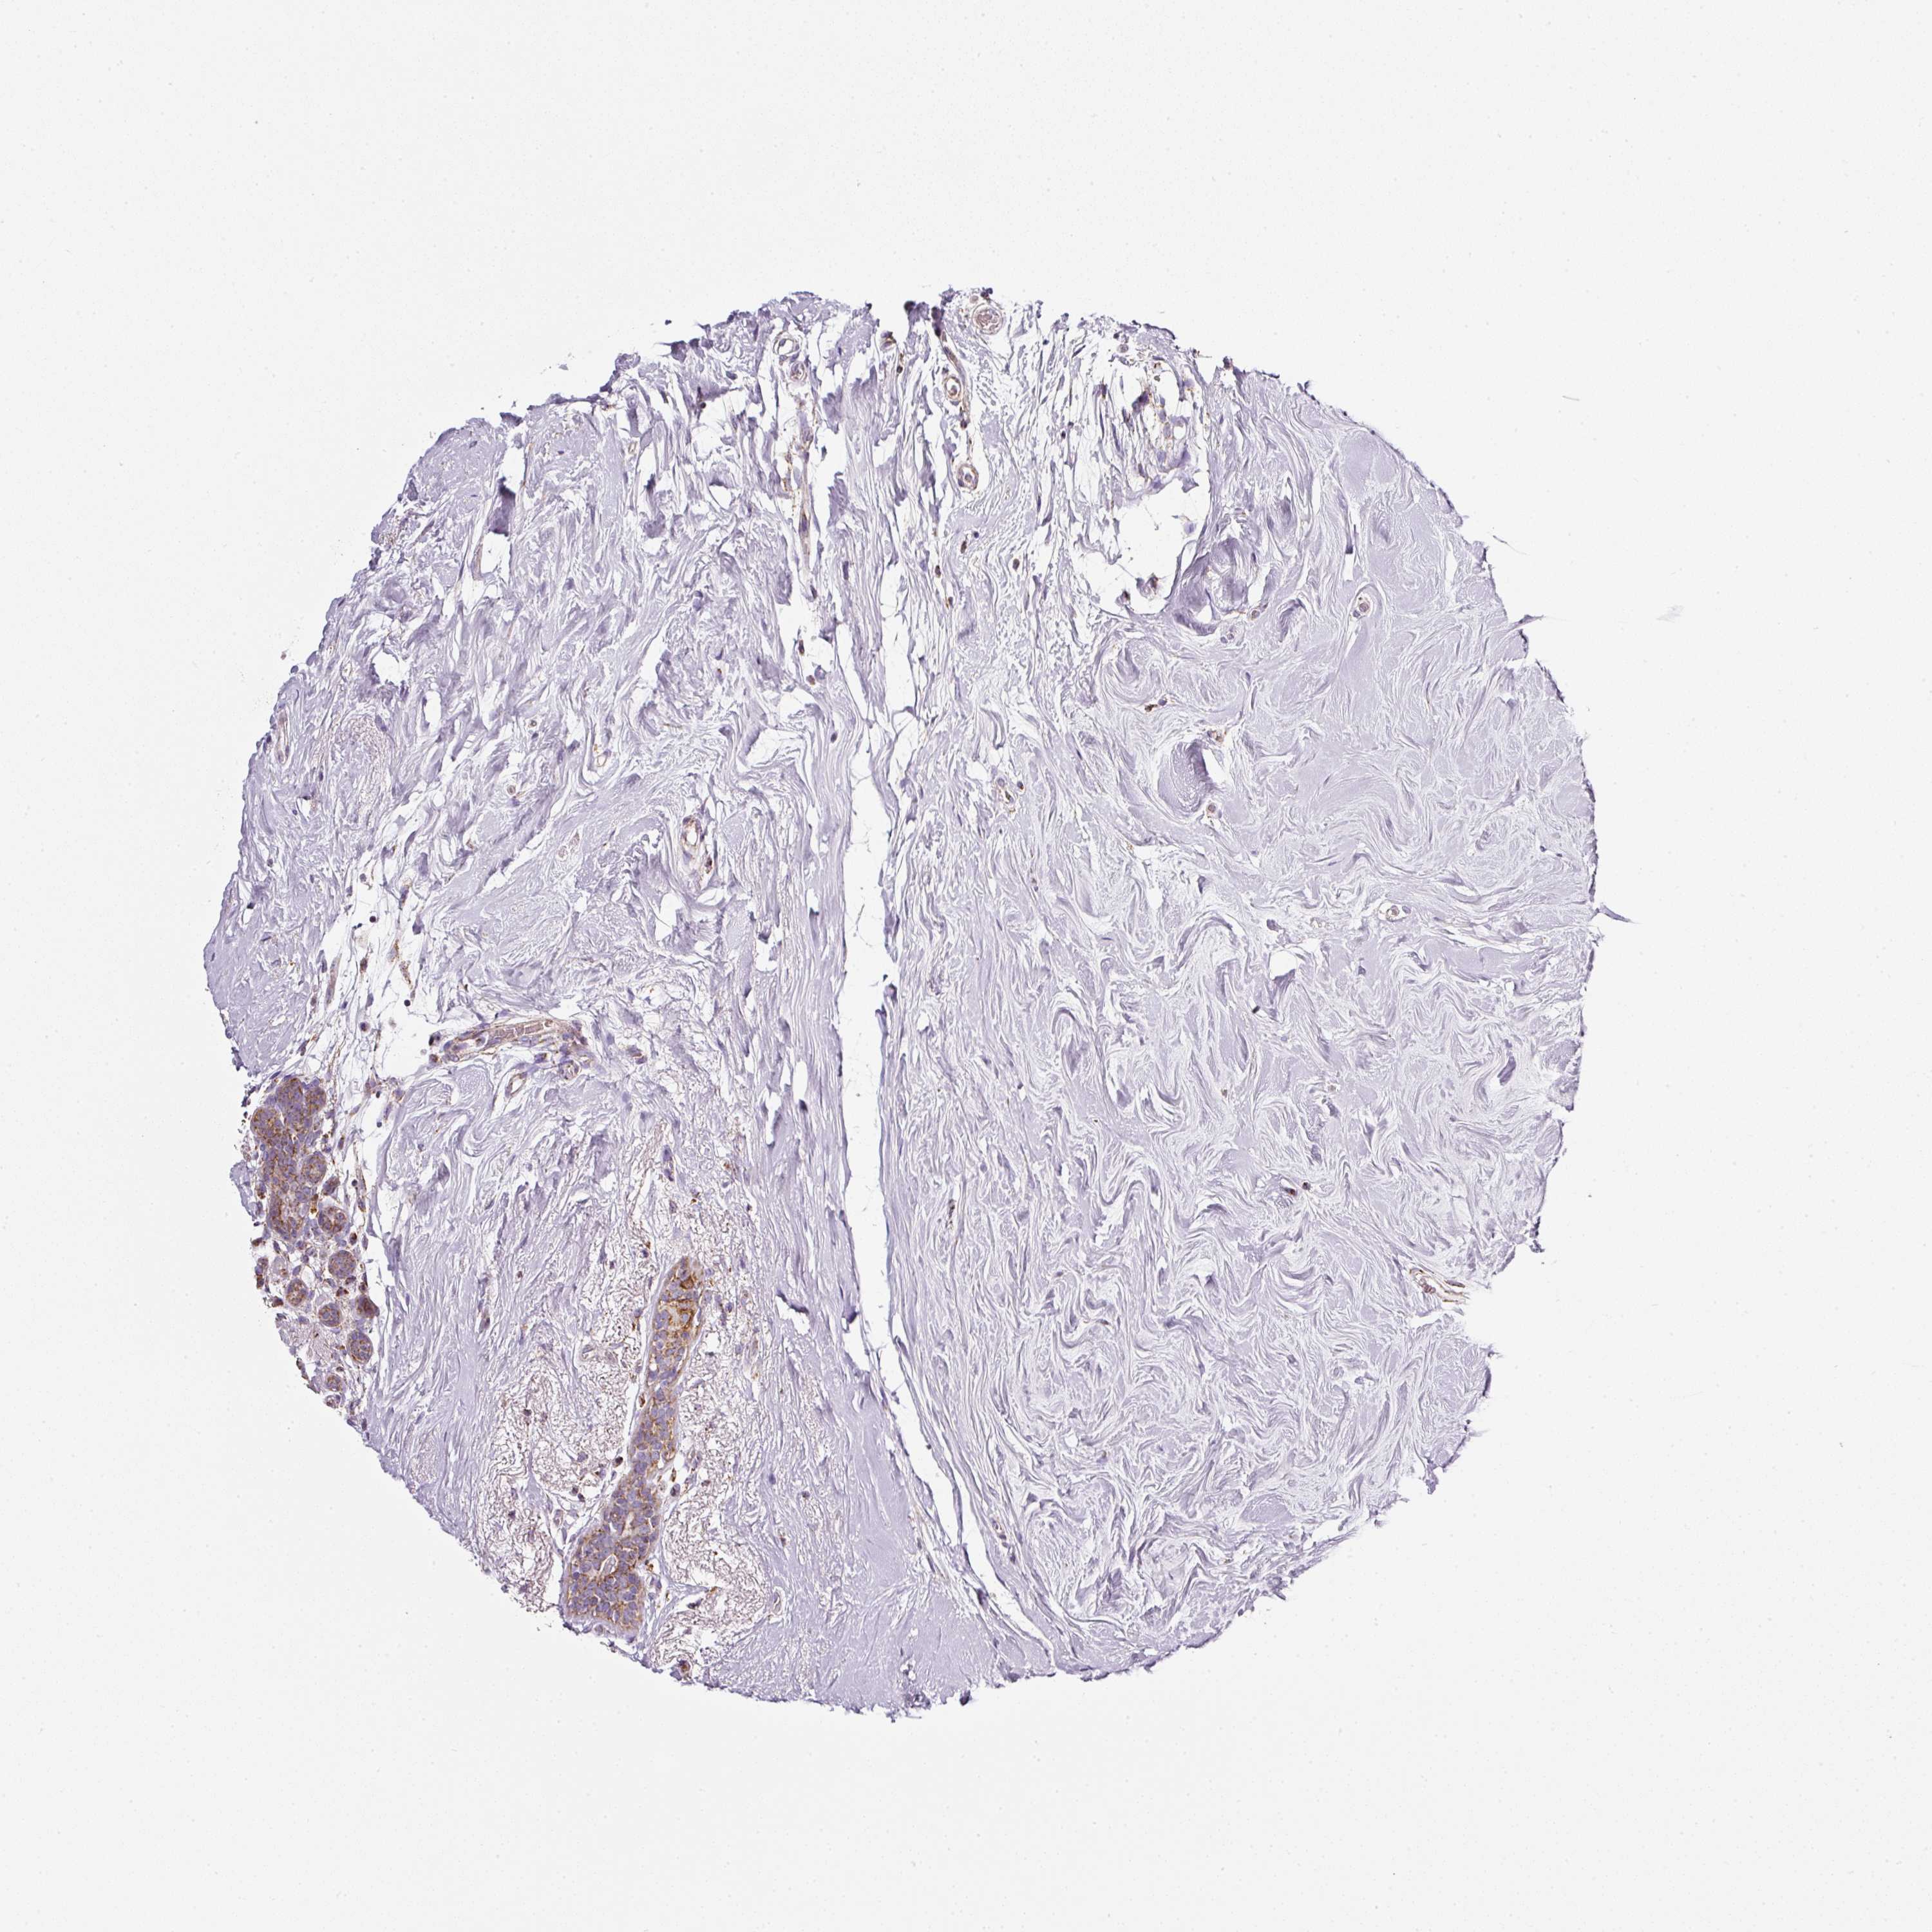

CANCER BREAST CANCER Show tissue menu

BRCA TCGA BRCA VALIDATION PROTEIN EXPRESSION